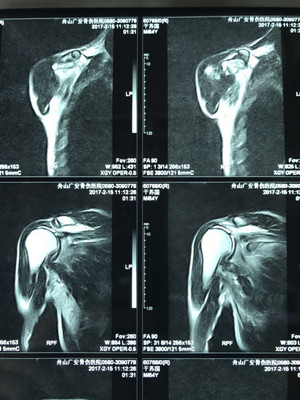

據(jù)了解,干大伯半年前因外傷導(dǎo)致頸椎外傷伴截癱,右肩關(guān)節(jié)脫位伴巨大肩袖斷裂,曾在廣安醫(yī)院接受頸椎手術(shù),術(shù)后恢復(fù)良好。后來,干大伯要求進一步對肩關(guān)節(jié)進行治療。廣安醫(yī)院副院長危立軍及運動醫(yī)學(xué)科主任羅軍對其進行詳細(xì)檢查后,認(rèn)為干大伯的右肩存在巨大不可修復(fù)肩袖撕裂伴嚴(yán)重的關(guān)節(jié)炎,肩袖的脂肪浸潤達(dá)到四級,治療上有一定的挑戰(zhàn)性,只能通過特殊類型的人工肩關(guān)節(jié)——反式全肩人工關(guān)節(jié)來重建關(guān)節(jié)功能。